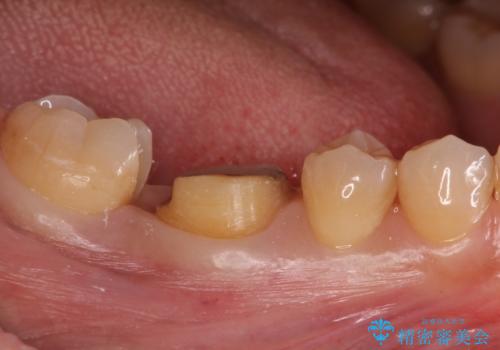

もう一つ奥の歯に関してもセラミックにやり替えたいとのことでしたので、こちらはインレーでの治療を行いました。

- 右下6:仮歯+セラミッククラウン/11,000円+110,000円 右下7:セラミックインレー/77,000円費用は治療当時の料金となります

残る歯が薄かったり、十分な量を確保できない場合はクラウンで治療した方が今後の破折リスクを抑えることができます。